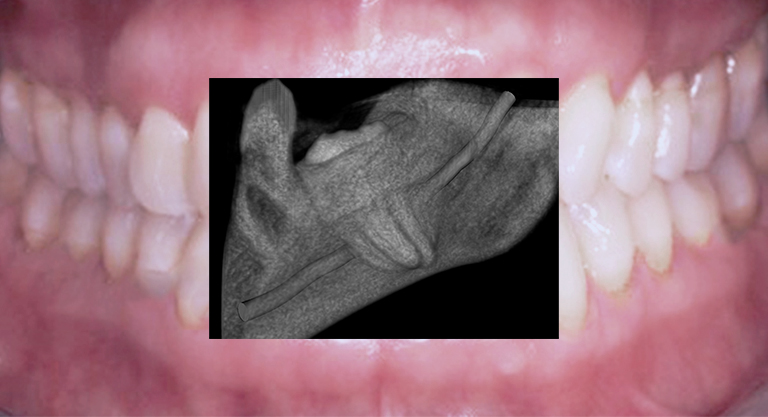

Diagnostik mittels 2-dimensionaler Bildgebung

3-dimensionale Volumentomographie DVT/OPT